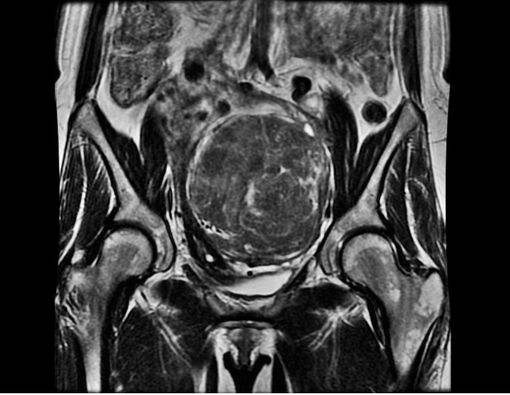

Dijelaskan oleh dr. Sepriani Timurtini Limbong, mioma uteri adalah pertumbuhan massa di bagian dalam atau luar rahim. Biasanya, massa ini berasal dari sel otot polos rahim.

Pertumbuhan massa ada yang menimbulkan gejala dan ada yang tidak, tergantung dari kondisi mioma uteri itu sendiri.

Mioma uteri adalah jenis tumor jinak, tidak bersifat ganas, dan tak selalu menandakan kanker.